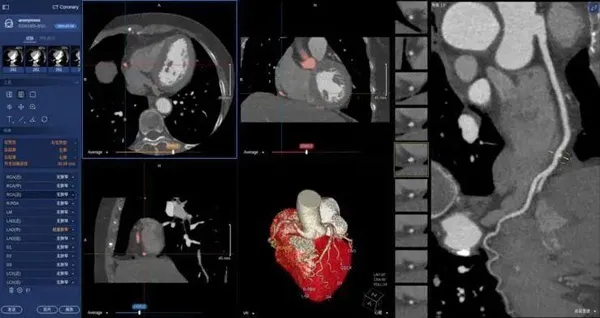

在醫(yī)學(xué)領(lǐng)域,機器視覺主要用于醫(yī)學(xué)輔助診斷。首先采集核磁共振、超聲波、激光、X射線、γ射線等對人體檢查記錄的圖像,再利用數(shù)字圖像處理技術(shù)、信息融合技術(shù)對這些醫(yī)學(xué)圖像進行分析、描述和識別,最后得出相關(guān)信息,對輔助醫(yī)生診斷人體病源大小、形狀和異常,并進行有效治療發(fā)揮了重要的作用。不同醫(yī)學(xué)影像設(shè)備得到的是不同特性的生物組織圖像,如X射線反映的是骨骼組織,核磁共振影像反映的是有機組織圖像,而醫(yī)生往往需要考慮骨骼有機組織的關(guān)系,因而需要利用數(shù)字圖像處理技術(shù)將兩種圖像適當(dāng)?shù)丿B加起來,以便于醫(yī)學(xué)分析。